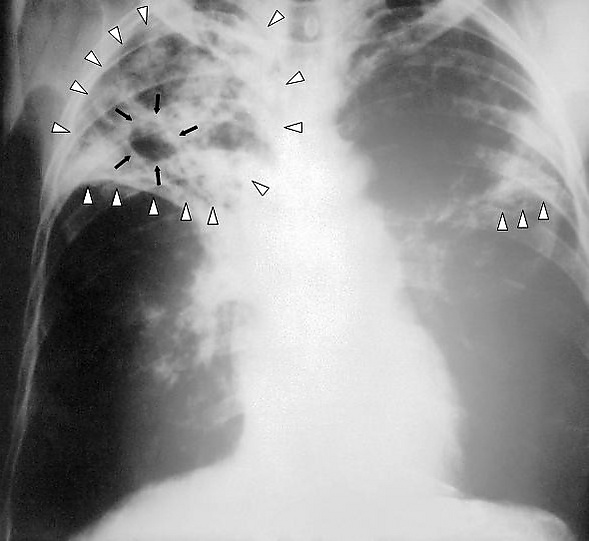

Туберкулома (лат. tuberculum — бугорок, -ωμα от ὄγκωμα — опухоль), или казеома лёгких — своеобразная форма туберкулёза лёгких, на рентгеновском снимке имеющая сходство с опухолью, отсюда и её название.

Диагностика туберкулёза основана на флюорографии, рентгенографии и компьютерной томографии поражённых органов и систем, микробиологическом исследовании различного биологического материала, кожной туберкулиновой пробе (реакции Манту), а также методе молекулярно-генетического анализа (полимеразная цепная реакция) и др.